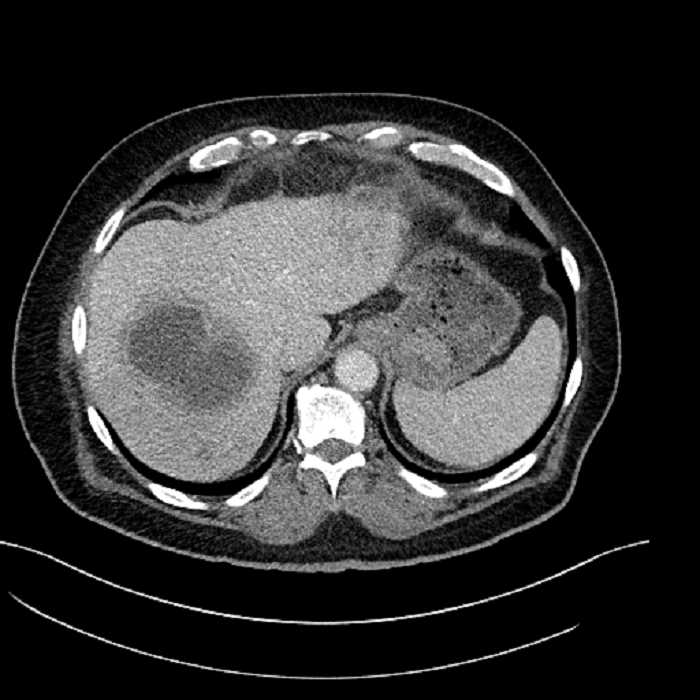

• Large fluid density structure in hepatic segments 7 and 8 measuring 10 x 7 x 7 cm with internal septation and circumferential ill-defined low density compatible with edema

• Peripherally enhancing subcapsular collections along the anterior margin of the left hepatic lobe measuring 3 x 1 cm and 2 x 1 cm

• Clearly marginated fluid density structure in segment 7 and several other scattered tiny hypodensities, which likely represent cysts

• Hepatic abscess

Acute sigmoid diverticulitis complicated by a small contained perforation and a large abscess in the right hepatic lobe. Additional small subcapsular abscesses along the anterior margin of the left hepatic lobe.

• The classic CT imaging appearance is a double target sign with internal low density surrounded by an internal enhancing rim (capsule) and a low density external rim (edema)

Hepatic abscess showing the double target sign with low density internally surrounded by a thin inner enhancing rim (red arrow) and ill-defined outer low density rim (yellow arrow). Blue arrow indicates an internal septation. Red arrows: additional smaller subcapsular abscesses. Red arrow: focal contained perforation associated with diverticulitis.